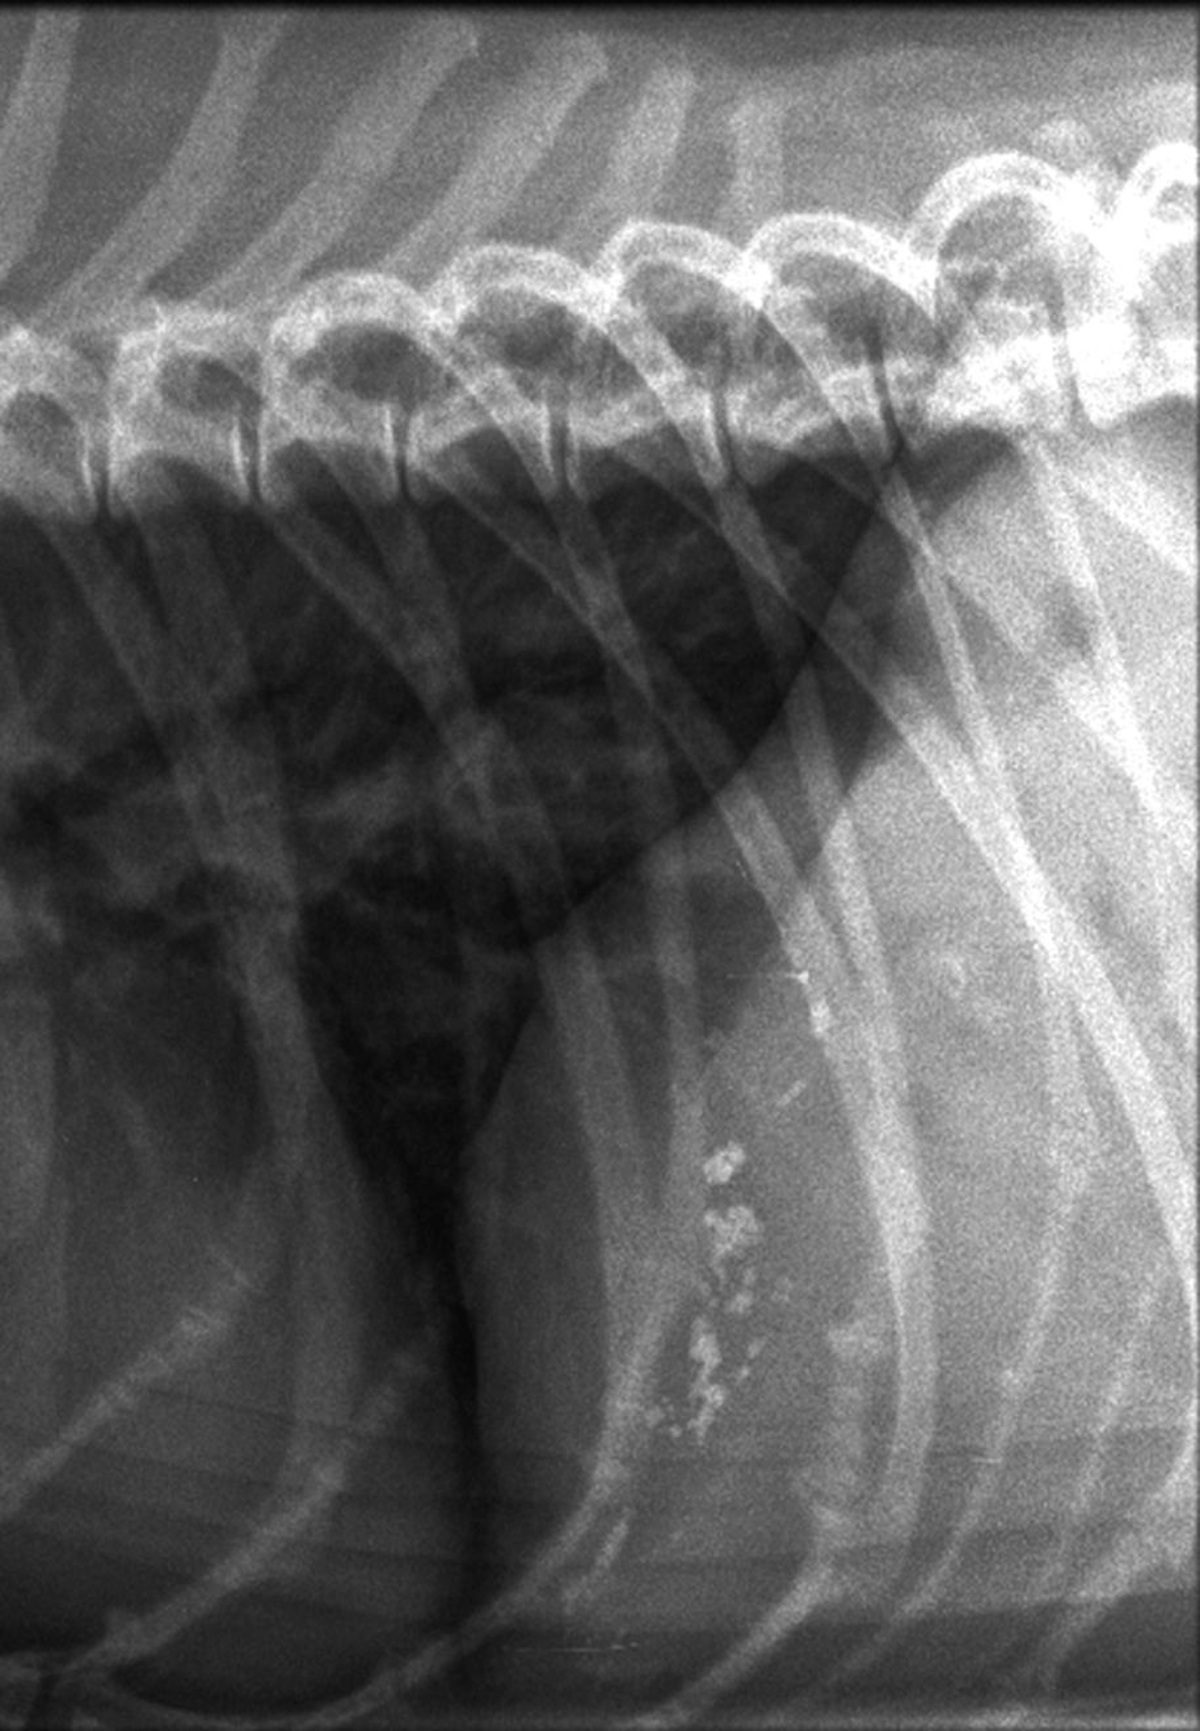

Hepatomegaly in dogs is typically recognized during presentation for nonspecific signs such as weakness, lethargy and inappetence These patients are sometimes jaundiced Causes infectious and toxic causes are typically associated with younger animals while neoplastic and cardiac causes are seen more frequently in older dogsSpleen left upper quadrant;1 N Y State J Med 1968 Feb 1;68(3) Fever, constitutional symptoms, hepatosplenomegaly, and abnormal chest xray rilm Bruno MS, Ober WB

Liver Hepatomegaly Cushing S Disease Radiograph Lateral Illustration Dogs Vetlexicon Canis From Vetlexicon Definitive Veterinary Intelligence

The Liver And Spleen Veterian Key

Diagnostic Imaging Of Canine Hepatobiliary Affections A Review